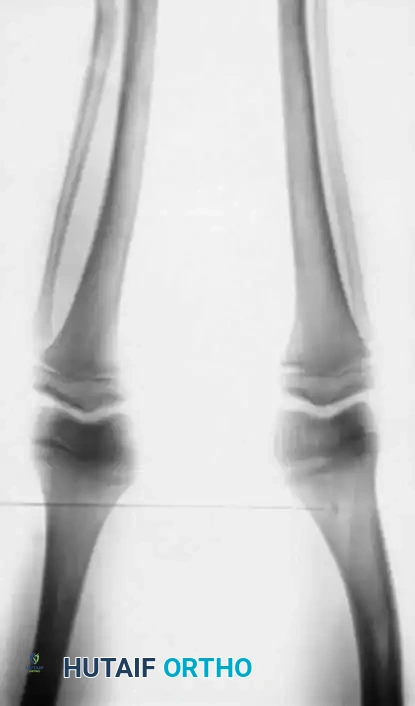

Image

Fig. 29-38 Vitamin D–deficient rickets. A, Standing radiograph of a young child with nutritional rickets resulting from severe vitamin D deficiency, demonstrating classic metaphyseal flaring and varus bowing. B, The same child 18 months later, demonstrating profound spontaneous correction of the mechanical axis following targeted treatment with vitamin D supplementation and corrective bracing.